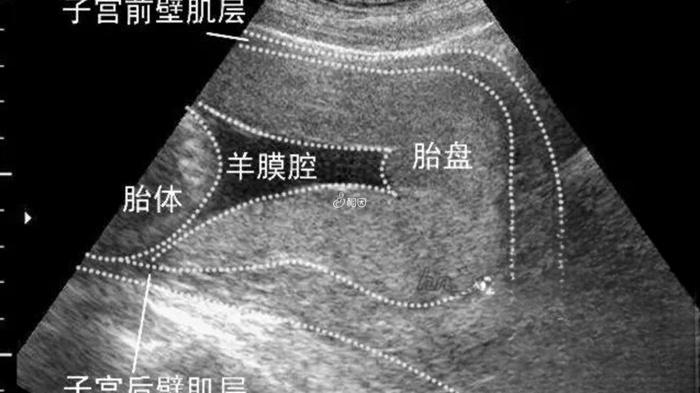

男孩一般在前壁还是后壁?附胎盘位置看胎儿性别的方法

2025-11-06 14:33

怀孕妈妈知识宝典